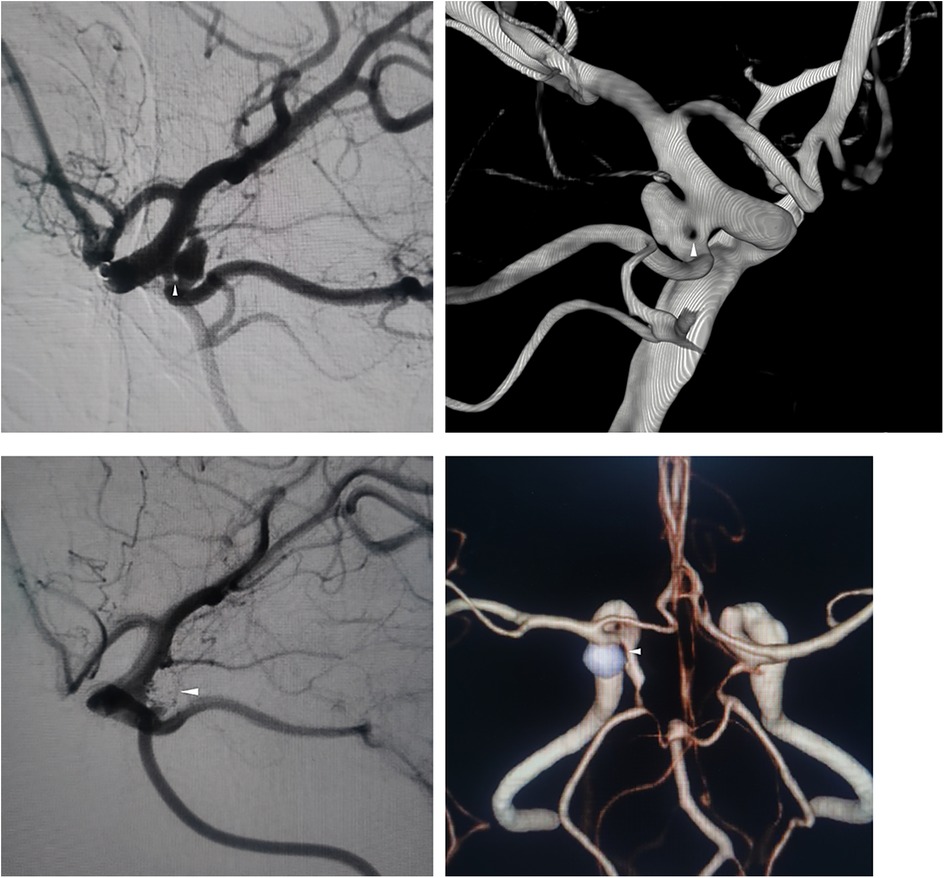

A 65-year-old woman presented to a local hospital with chronic, persistent dizziness. There was no history of acute severe headache, meningismus, or decreased consciousness to suggest aneurysm rupture. Cranial computed tomography angiography (CTA) demonstrated a left posterior communicating artery (PCoA) aneurysm and internal carotid artery stenosis. Non-contrast CT showed no evidence of subarachnoid hemorrhage. Following 4 days of conservative observation, she was discharged but continued to experience intermittent dizziness without associated symptoms, prompting referral to our institution for definitive aneurysm management. Digital subtraction angiography (DSA) at our center confirmed a 0.8 mm fenestration in the left PCoA with a coexisting saccular aneurysm measuring 3.52 × 2.12 × 2.93 mm at the same location (Figure 1A). Three-dimensional DSA reconstruction further characterized the aneurysm morphology (Figure 1B). Her medical history included untreated hypertension for 3 years, with no history of diabetes, coronary artery disease, renal disorders, tobacco use, or alcohol consumption. Neurological examination revealed an alert and oriented patient (GCS 15) with pupils equal, round, and briskly reactive to light. A comprehensive cranial nerve examination was normal; specifically, she had no diplopia, ptosis, or disconjugate gaze to suggest oculomotor or other cranial nerve palsy. She exhibited full bilateral extremity strength (grade V), normal muscle tone, and no focal neurological deficits.

Figure 1. (A) Preoperative DSA shows left PCoA fenestration (arrow) and aneurysm. (B) 3D-RA confirms single-segment fenestration. (C) Postoperative DSA demonstrates complete aneurysm occlusion. (D) 12-month follow-up CTA confirms no recurrence.

Endovascular embolization was performed using a dual-microcatheter technique. An initial 4 × 10 cm framing coil was deployed, followed by sequential placement of four additional coils ranging from 2 × 4 cm to 1.5 × 1 cm. Through intentional coil protrusion into the aneurysmal limb of the fenestrated segment, parent vessel occlusion was achieved while preserving flow through the contralateral channel. Final angiography demonstrated complete aneurysm occlusion classified as Raymond-Roy Class I (Figure 1C).

2.5 Outcome and follow-up

Twelve-month postoperative CTA surveillance revealed no recurrence. The patient remained neurologically intact with a modified Rankin Scale score of 0 (Figure 1D).